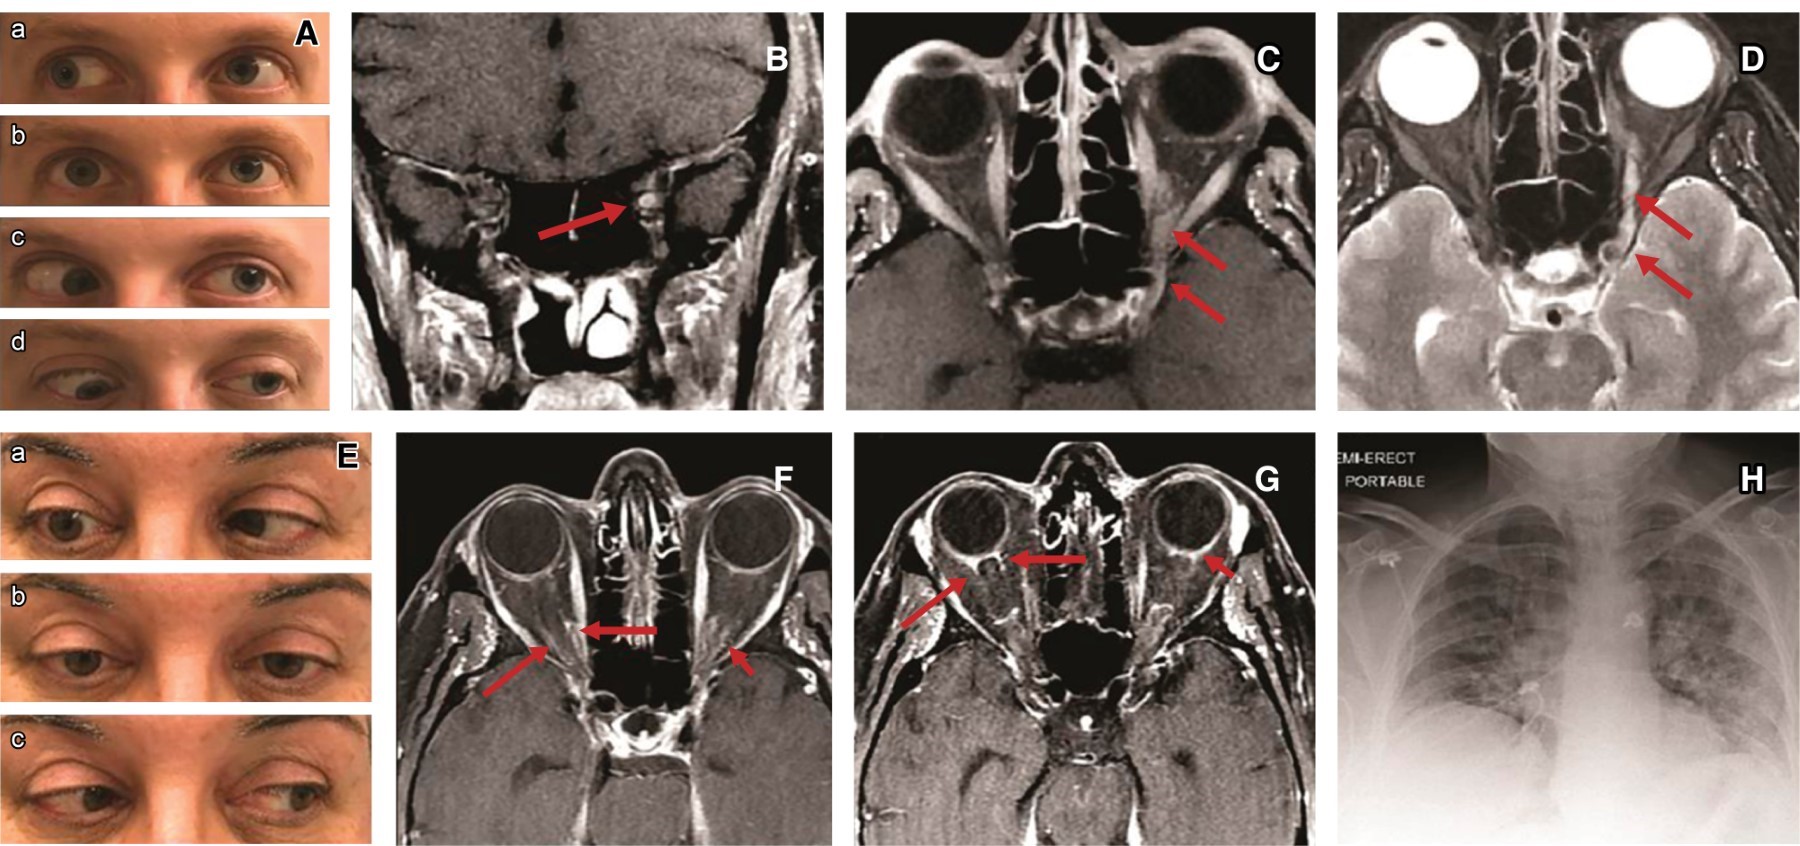

Caso clínico. Con afectación ocular. Mujer de 49 años que refiere presencia de fiebre, astenia, mialgias y cefaleas de tres días de evolución. El estudio (PCR) para SARS-CoV-2 fue positivo. El cuadro clínico, la IRM con proceso inflamatorio en el nervio óptico izquierdo y seno cavernoso derecho, y la radiografía de tórax reveló neumonía multifocal (Figura 3).

Figura 3